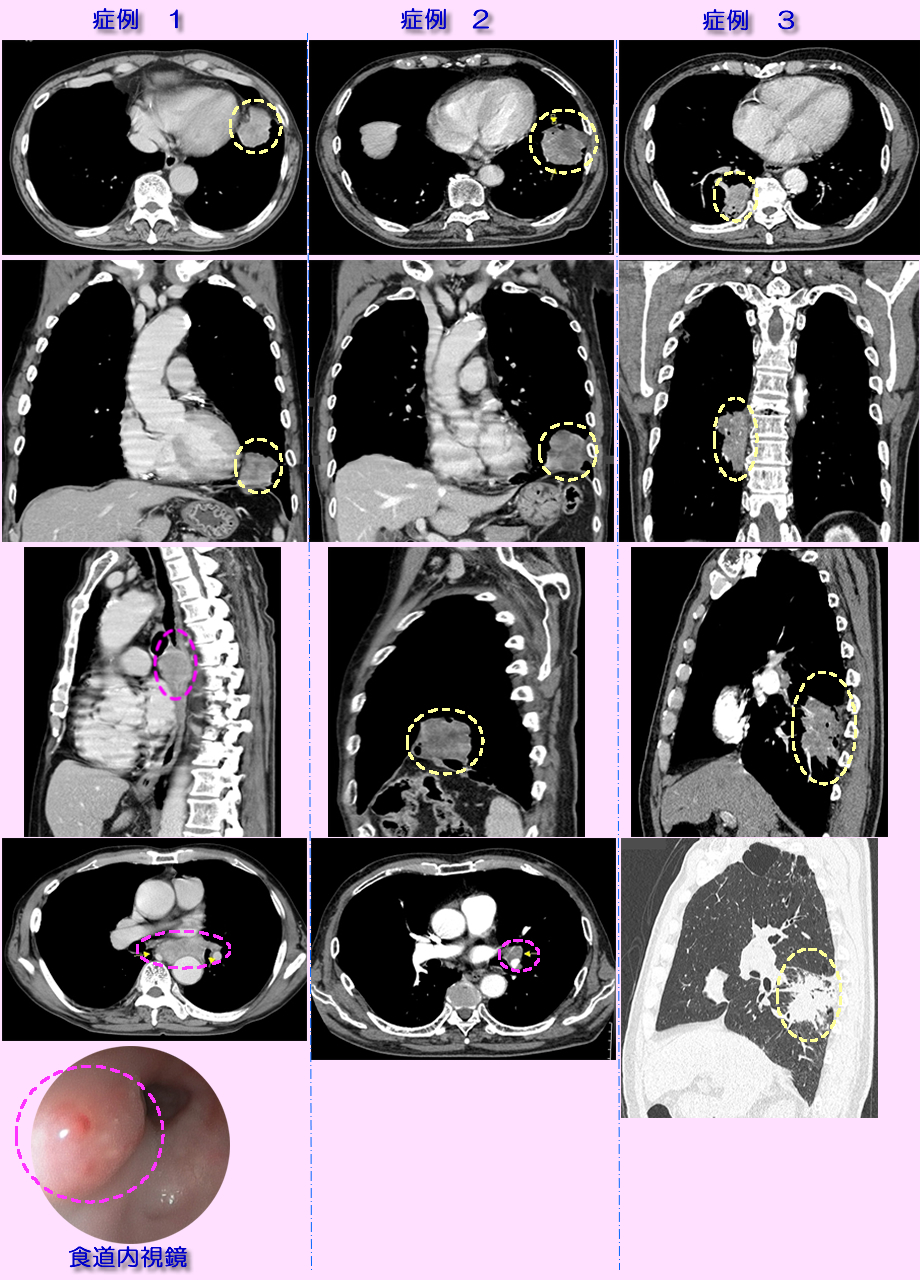

| 症状 | 掲載症例1は1ヶ月以上続く咳と嚥下時の痛みで来院、症例2は軽い胸部痛で受診、症例3は背部痛で受診 |

| 診断 | 画像診断には胸部X線撮影、詳細な診断にはCT、MDCT、PET-CTなどを用います。腫瘍の組織性状(がんの種類)の確定には喀痰の細胞診、気管支鏡を用いた腫瘍部位の生検、経胸壁的な穿刺針生検などが行われます。下記掲載画像は3次元的な任意断面画像が得られるMDCTにるものです。腫瘍の性状(血管発達状況)推定や、肺血管と腫瘍の区別、位置関係を明瞭にするため造影剤使用下に撮影したもです。黄色の破線内ががんの部位です。がんの種類は生検、血液腫瘍マーカから扁平上皮がんでした。がんの縦隔部位や肺門リンパ節への転移を適切な画像断面から評価します。その転移の有無、広がり部位から、手術の可能性、放射線治療か抗がん剤唖治療か、その併用かなどの治療方針を判断します。ピンクの破線で囲む部位に縦隔、リンパ節への転移を認めます。症例1は縦隔部位へ転移したがんは食道を圧迫し、大動脈周囲にも浸潤しており、食道内視鏡検査(最下段の画像)ではがんが食道内に膨隆して圧迫し、浅い潰瘍を生じています。嚥下時の胸の痛みや食物停滞感の原因が理解されます。本例は手術不能で放射線・化学療法が行われました。症例2もピンンクの楕円で示す部位にリンパ節転移を認めます。症例3は放射線療法が開始され3ヶ月後、他界されました。 |